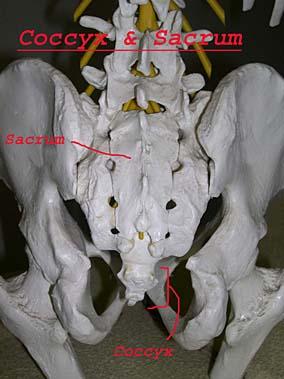

The coccyx is at the very bottom part of the spine, and consists of four or more very small bones stuck together. The coccyx initially joins with the sacrum through a small disc, and is also connected to the sacrum and pelvis with ligaments. In the coccyx, the vertebrae generally fuse together in early adulthood and may also fuse with the sacrum. It is not clearly understood which part of the coccyx causes pain; probably the ligaments or the joint cause the pain.